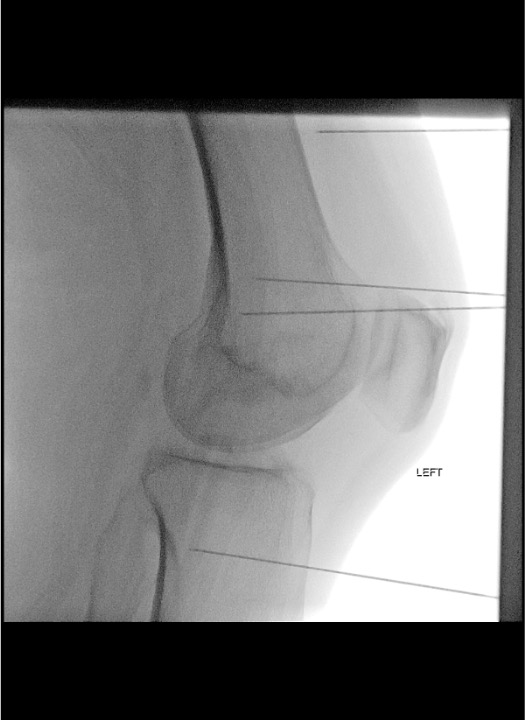

Lateral View Essentials

- Superimpose condyles on lateral view for accurate depth assessment

- Tip should project at the mid-depth of the condyle

- Too anterior = anterior fat pad / anterior capsule โ incorrect

- Too posterior = posterior capsule, popliteal vessels, neural structures โ incorrect and dangerous